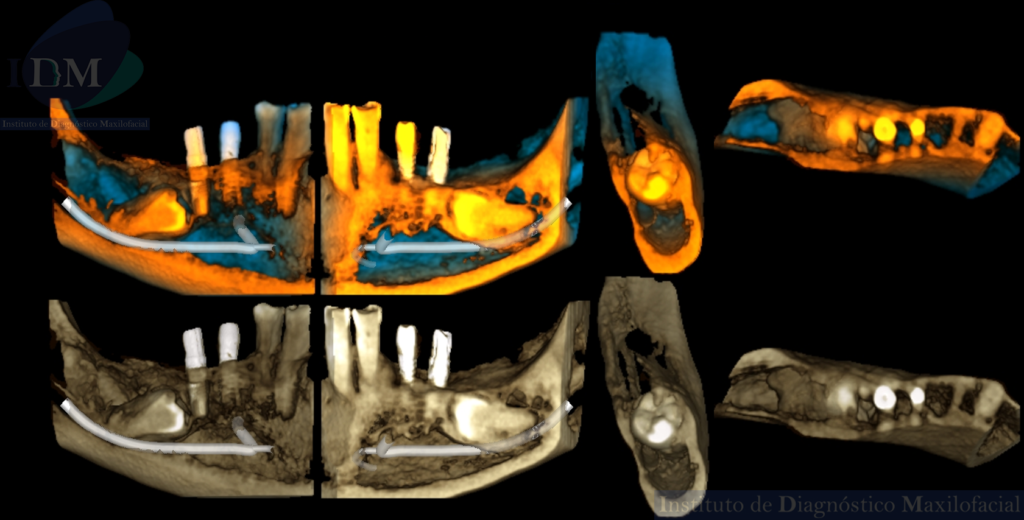

RECONSTRUCCIÓN 3D

A la evaluación de la radiografía panorámica se evidencia reabsorción ósea alveolar bimaxilar, edéntulo parcial bimaxilar y presencia de múltiples implantes con prótesis sobre implantes así como tratamientos restaurativos. Siendo lo más destacado una molar retenida en cuerpo mandibular izquierdo, la cual esta mesioangulada.

Siendo así que en la tomografía volumétrica de haz cónico se evidencia una hipercementosis radicular, con los segmentos radiculares contactando con el conducto dentario inferior. Finalmente se evidencia un borramiento del espacio del ligamento periodontal compatible con anquilosis dentaria.

Anquilosis dentoalveolar